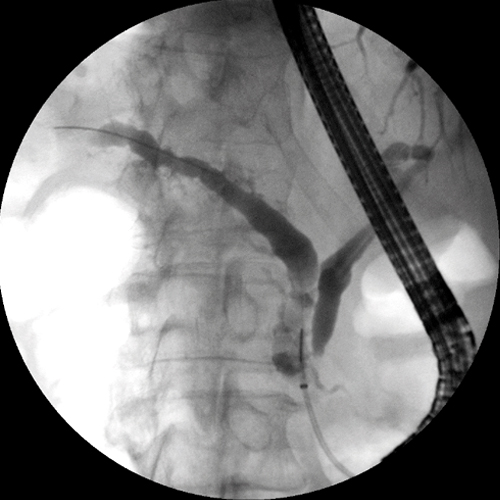

- Innere Medizin, Gastroenterologie